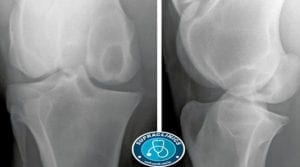

يُمكن تشخيص الكيس العظمي عادة عن طريق فحص الأشعة السينية لعظم طفلك.

هذا سوف يُسلط الضوء على أي تجاويف مجوفة أو كسور في العظم.

في كثير من الحالات لا يُمكن إكتشاف كيس العظام إلا عن طريق الصدفة عند إستخدام الأشعة السينية لتشخيص حالة ليس لها صلة.